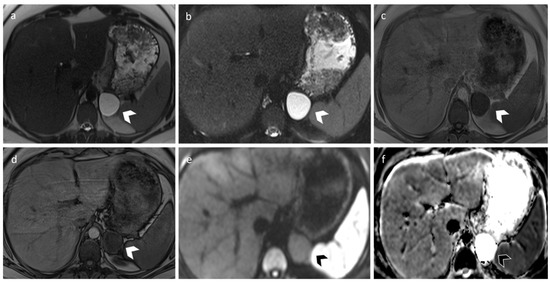

3.3. Carcinoma